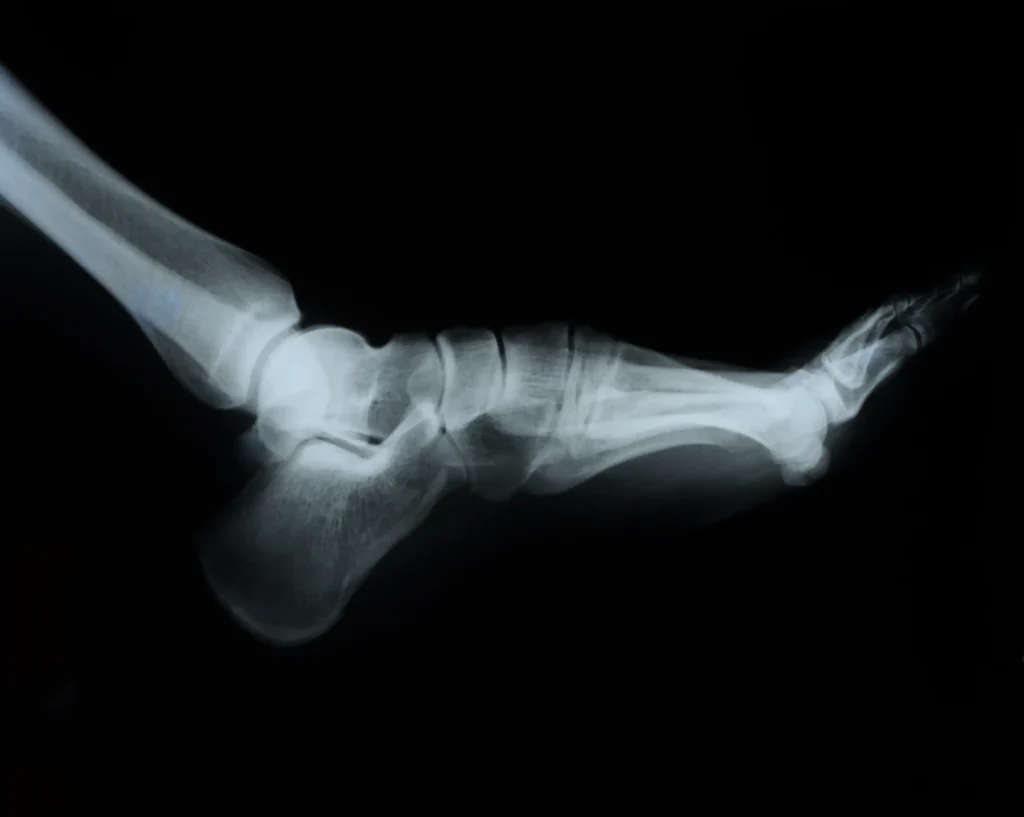

La exploración física del pie es un componente esencial de la historia clínica podológica. Esta evaluación incluye:

- La inspección del estado de la piel y uñas.

- Un análisis de la postura del paciente.

- Un análisis detallado de los pies y tobillos para identificar cualquier anormalidad que pueda estar afectando la salud del paciente.

Además, la exploración física debe considerar aspectos como la alineación del pie y la distribución del peso al caminar. Este análisis ayuda a identificar problemas biomecánicos que puedan estar contribuyendo a las molestias del paciente. Documentar estos hallazgos es crucial para un diagnóstico preciso y para la formulación de un plan de tratamiento efectivo.